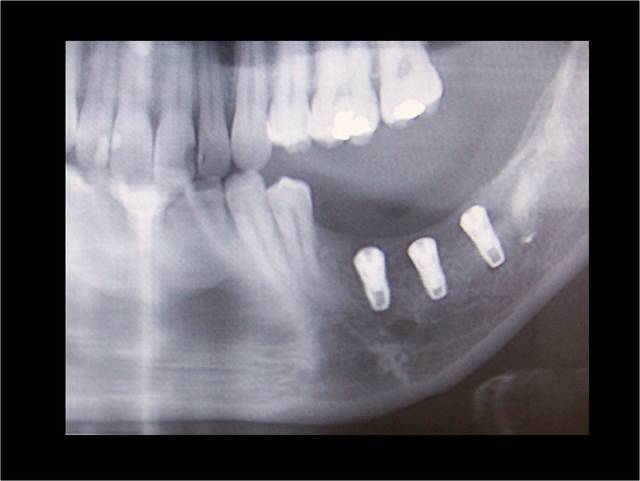

2010.04.positdental - Eugenol

le jaune je sais faire